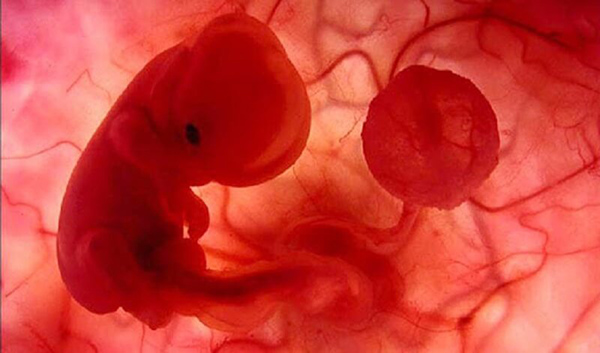

Theo nghiên cứu về sự tiến triển của bào thai trong bụng mẹ, ở tuần thứ 5 thì tim thai sẽ hình thành. Tim thai ở giai đoạn này có kích cỡ rất nhỏ, bao gồm các ống dẫn đơn giản và chỉ bé bằng hạt gạo. Khi đến tuần thứ 7, tim thai đã lớn dần và bắt đầu phân thành 2 buồng tim là buồng trái và buồng phải.

Tim bào thai sẽ tiếp tục tiến triển và hoàn thiện dần. Đến tuần 12 đến tuần 125, tim thai sẽ hoàn thiện và đập mạnh mẽ. Khi siêu âm và sử dụng các thiết bị y tế, mẹ bầu có thể nghe rõ tiếng tim thai nhi đập.